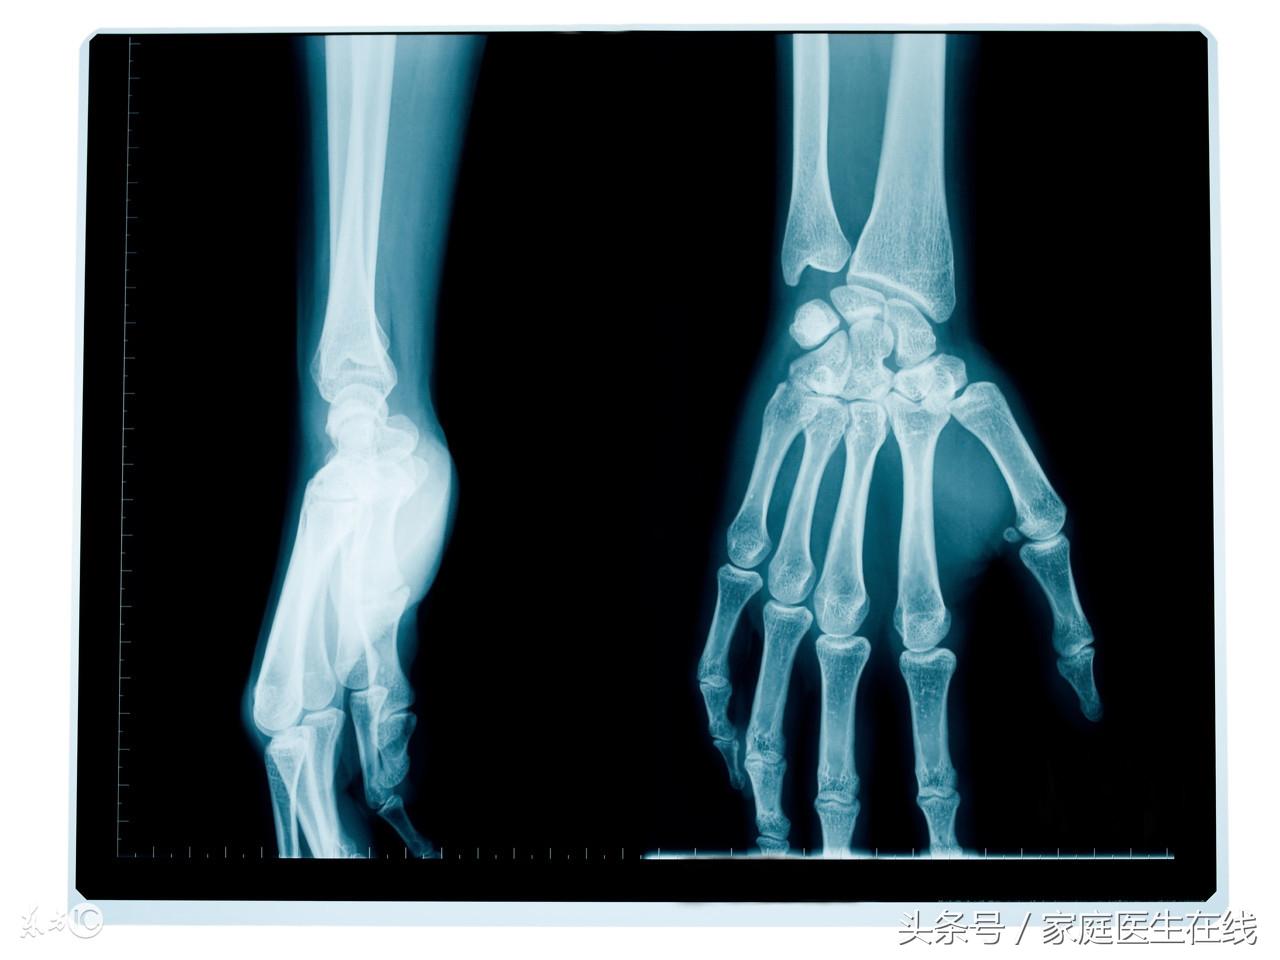

钙物质是人体中含量最多的矿物元素,同时也是人体再生育发展中所需要的一个物质。人类99%的钙元素都存在于骨头和牙齿上,还有剩下的1%的钙元素是存在于血液和肌肉这些组织中。